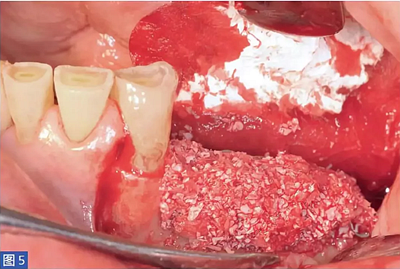

圖5:病例1. 在內(nèi)固定板限定空間中填塞移植物材料。

然后用手磨器械(Hu-Friedy)將收獲的骨塊進(jìn)行顆?;幚恚⑵渑cDBBM 和患者的靜脈血混合,形成凝膠狀的黏稠度。為了刺激骨的再生,在基骨嵴上鉆出微孔,以開(kāi)放骨髓腔。然后放置生物材料,填充骨壁和鈦板內(nèi)表面之間的整個(gè)空間。

然后用特定的微螺絲固定鈦板。當(dāng)鈦板固定穩(wěn)定后,開(kāi)始植入骨增量材料。本研究所述的6個(gè)病例中,脫蛋白牛骨骨基質(zhì)(DBBM;Bio-Oss,Geistlich)與患者自體骨結(jié)合使用。自體骨與DBBM 的比值約為50:50。骨移植物于口內(nèi)供區(qū)獲得,最好是在下頜骨升支基部區(qū)域。